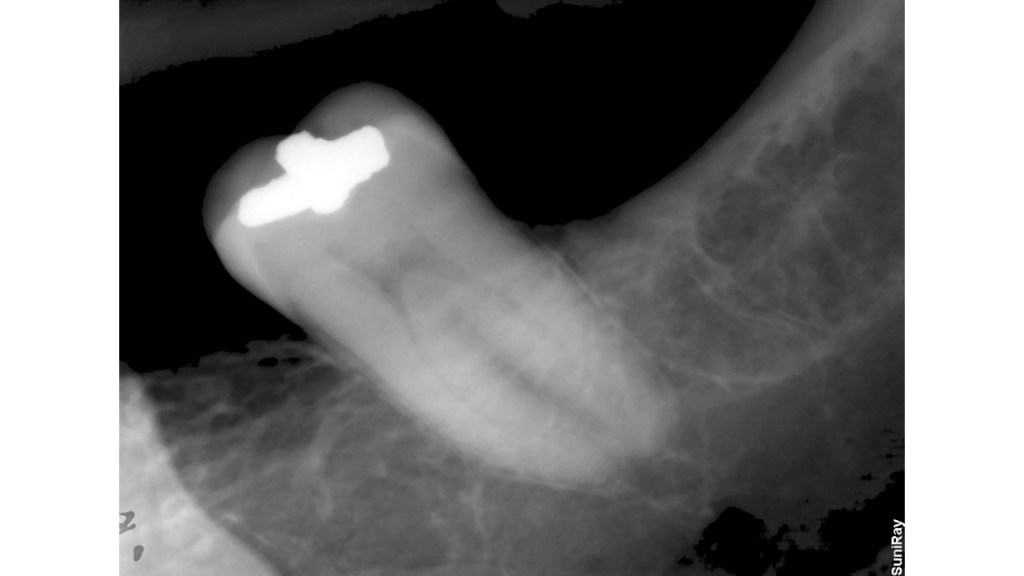

This is a “garden variety” endo. The best time to refer a case to an endodontist with a microscope is before the pulp has been touched. That way, the endodontist can control how much of tooth structure is removed to complete the endo. In this case, I had to chase all the cracks before restoring